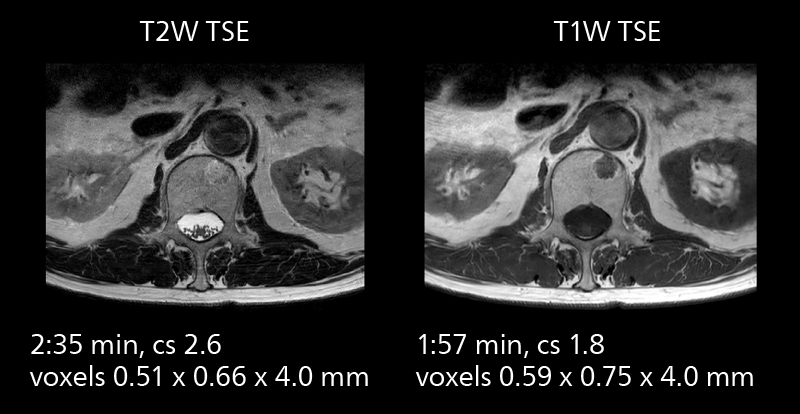

Crisp images are obtained with high resolution and short scan times using Elition X. A cyst can be seen.